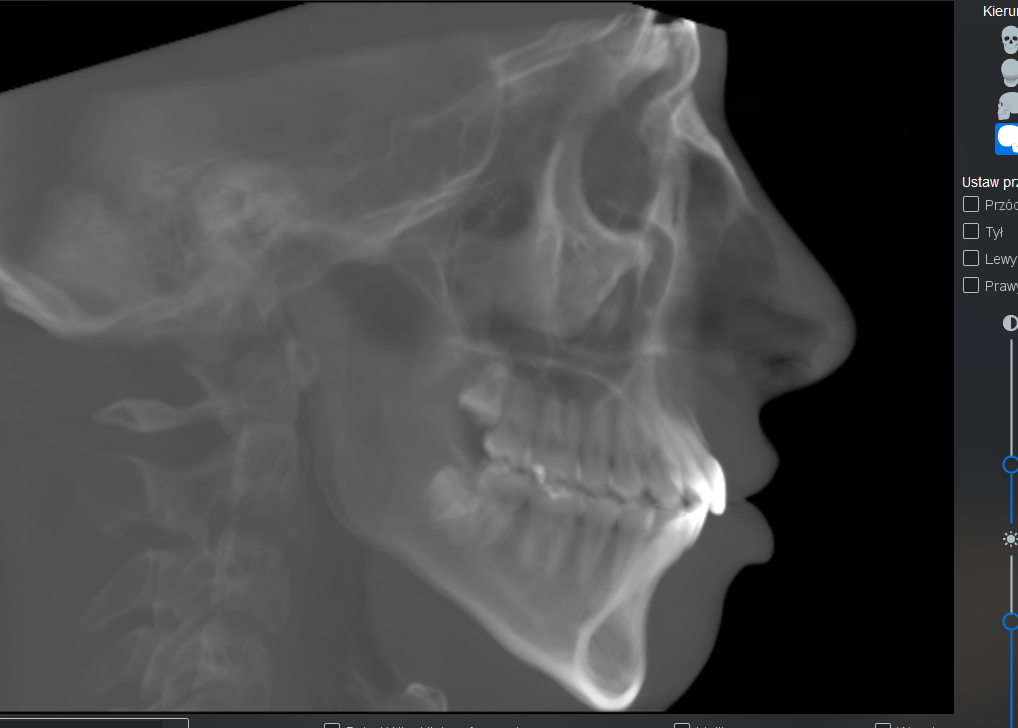

At least 4* of counter clockwise rotation on both jaws.

5mm+ advancement on both maxilla and mandible

7mm+ genioplasty

My jaw surgery movements are limited because of my natural unfortunate teeth position and a combination of other factors.

I have what some asian surgeons describe as a “protruding mouth.” However that type of protrusion is often related to the shape of the maxilla and is typically addressed by removing a portion of the maxilla, often together with tooth extractions which is very fucking dumb.

At least 4* of counter clockwise rotation on both jaws.

5mm+ advancement on both maxilla and mandible

7mm+ genioplasty

My jaw surgery movements are limited because of my natural unfortunate teeth position and a combination of other factors.

I have what some asian surgeons describe as a “protruding mouth.” However that type of protrusion is often related to the shape of the maxilla and is typically addressed by removing a portion of the maxilla, often together with tooth extractions which is very fucking dumb.